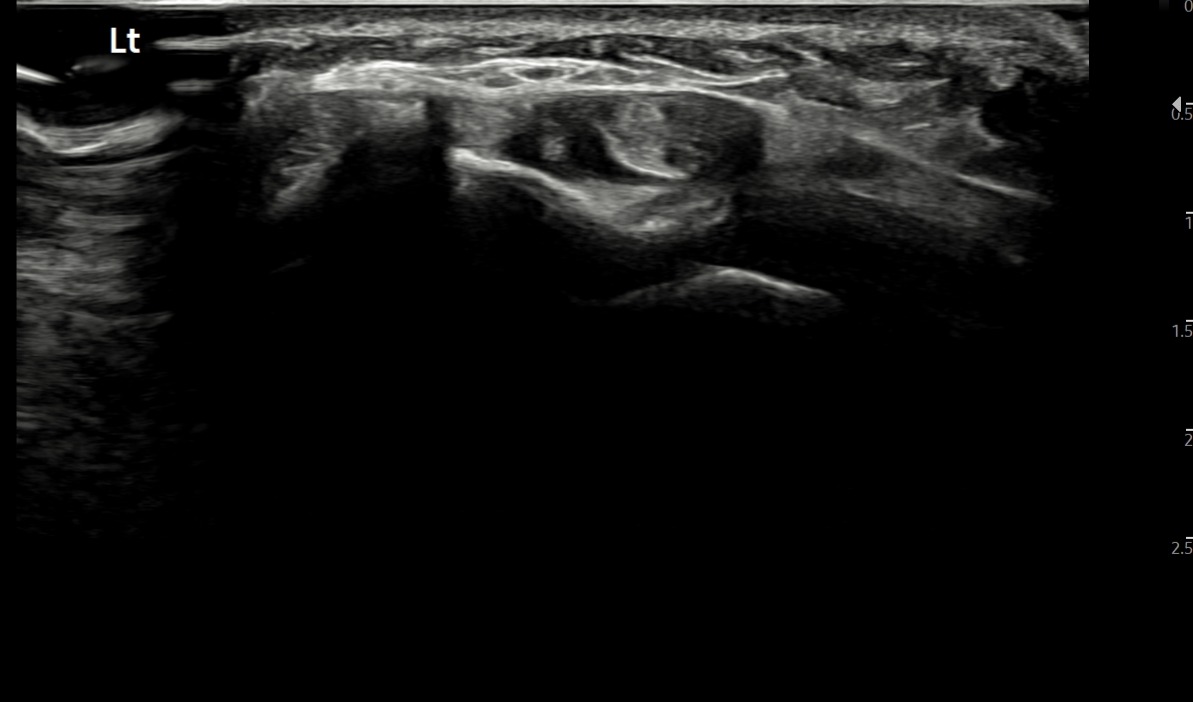

치료 후기에 사용된 전/후 검사 사진은 동일 인물의 결과이며 각 지점 동일 조건에서 촬영되었습니다.

개인에 따라 치료 결과에 차이가 있을 수 있으며, 부작용이 발생할 수 있습니다. 내원 후 충분한 상담을 받으시고 치료를 진행하시면 됩니다.

- 치료기간 : 25 . 5 . 13 ~ 25 . 6 25.

- 치료횟수 : 10 회, 한약 1개월 + 라이넥 10회 + 극초단파 10회

치료 전

치료 후